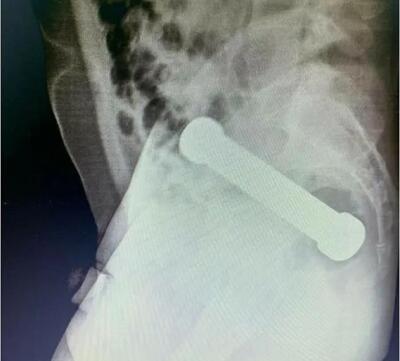

La radiografía reveló que la pesa tenía casi 8 pulgadas de largo (20 cm) y estaba alojada exactamente en la parte donde el colon se encuentra con el recto.

Los médicos decidieron chequear más a fondo y, tras un tanteo manual, sintieron un objeto extraño, de gran peso y tamaño, razón por la que realizaron una ecografía abdominal, descubriendo una pesa dentro del cuerpo.